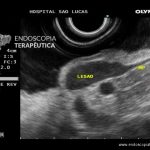

GIST gástrico